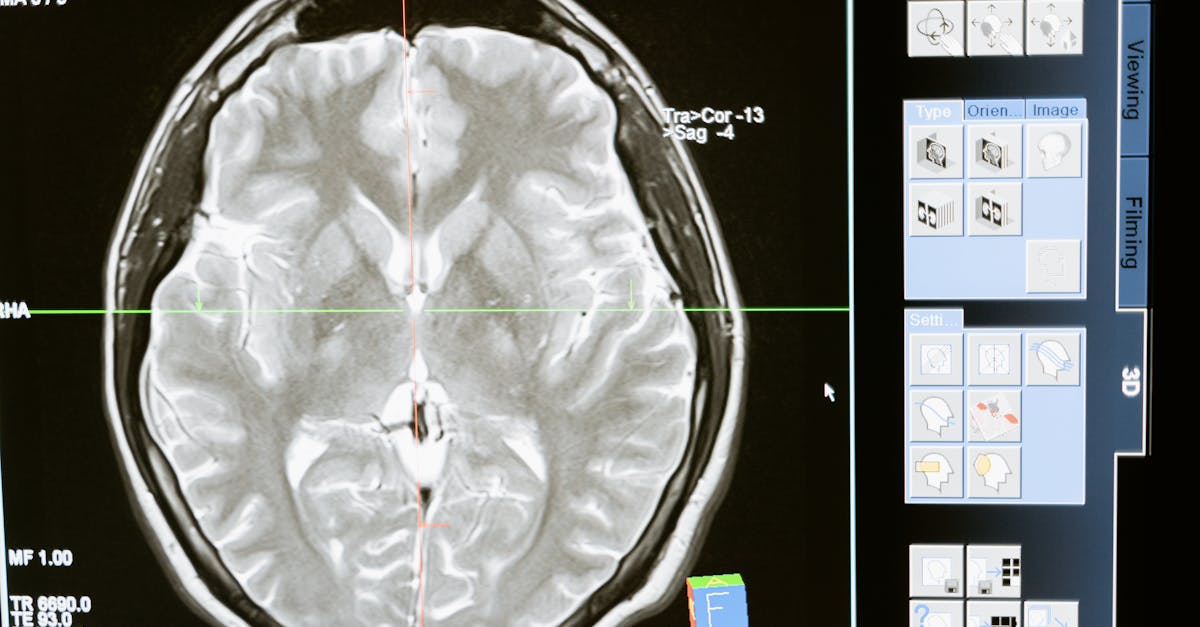

Une fois l’examen physique effectué, des tests diagnostiques peuvent être recommandés. Ces tests incluent souvent des examens d’imagerie comme des IRM ou des scanners. Ces outils fournissent des images détaillées permettant d’analyser la structure des disques et de la colonne vertébrale.

- Imagerie par résonance magnétique (IRM) : utile pour visualiser les structures internes

- Scanner : aide à détecter des anomalies osseuses

| Tests diagnostiques | Analyse sanguine et imageries médicales, comme IRM ou scanner. |

En fonction des observations de l’examen physique, le praticien peut décider d’administrer des tests diagnostiques supplémentaires. Ceux-ci peuvent inclure des analyses sanguines pour vérifier des inflammations ou des infections, des tests d’imagerie médicale comme des radiographies, IRM ou scanners pour visualiser les structures internes de la colonne vertébrale. L’imagerie permet souvent de détecter des anomalies telles que des hernies discales ou des tassements vertébraux qui sont des indicateurs potentiels pour une décompression névralgique. Ces outils diagnostiques modernes, couplés à l’expertise clinique, favorisent un diagnostic plus précis.